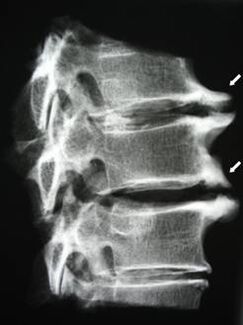

Dans les premiers stades, l'ostéochondrose est détectée par IRM.. Par la suite, la pathologie peut être diagnostiquée par radiographie. Sur les radiographies de la colonne cervicale, on note une diminution de la distance entre les vertèbres, des modifications pathologiques des facettes articulaires et une ostéophytose.

| Ostéochondrose cervicale | L'apparition de changements pathologiques dans un ou plusieurs segments de mouvement de la colonne vertébrale. Altération de la mobilité vertébrale, développement de syndromes douloureux myofasciaux et pincement des racines vertébrales. | Douleurs, paresthésies et altérations motrices dans la région cervicale, qui s'étendent au cou et aux membres supérieurs. Détection de changements caractéristiques de la colonne vertébrale par IRM et rayons X (ostéophytes, diminution de la distance entre les vertèbres, signes de lésions des articulations intervertébrales) |